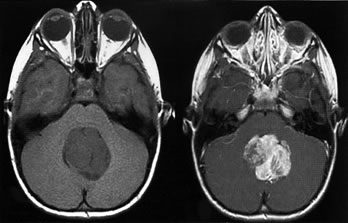

Медуллобластома (medulloblastoma). Злокачественная опухоль из медуллобластов, незрелых клеток глии, локализующаяся обычно в черве мозжечка, который находится рядом с четвертым желудочком мозга. Характерны симптомы раковой интоксикации, нарастающей интракраниальной гипертензии и мозжечковой атаксии. Диагноз ставится на основании клинической картины, результатов анализа спинномозговой жидкости, ПЭТ, КТ или МРТ, биопсии. Лечение включает хирургическое удаление опухоли, восстановление нормальной циркуляции спинномозговой жидкости, лучевую и химиотерапию.

С диагностический целью врачом неврологом производится суммарная оценка данных неврологических, офтальмологических, ликворологических исследований, а также результатов КТ или МРТ головного мозга. Для комплексного обследования и поставки диагноза медуллобластомы могут потребоваться результаты следующих видов исследований: общий анализ крови, общий анализ мочи, биохимия крови; осмотр офтальмолога, который при проведении офтальмоскопии выявляет застойные диски зрительных нервов, свидетельствующие об интракраниальной гипертензии; нейросонография у детей с незакрытыми родничками, обеспечивающий наиболее раннюю диагностику опухоли; компьютерная томография (КТ), которая дает возможность определить точно местоположение и размеры опухоли, степень инфильтрации окружающей мозговой ткани; магнитно-резонансная томография (МРТ), позволяющая выявить самые незначительные изменения в структуре головного мозга; позитронно-эмиссионная томография (ПЭТ), оценивающая процесс метастазирования; определение онкомаркеров в крови; биопсия (гистопатологический анализ тканей) для выставления окончательного клинического диагноза; консультация нейрохирурга.